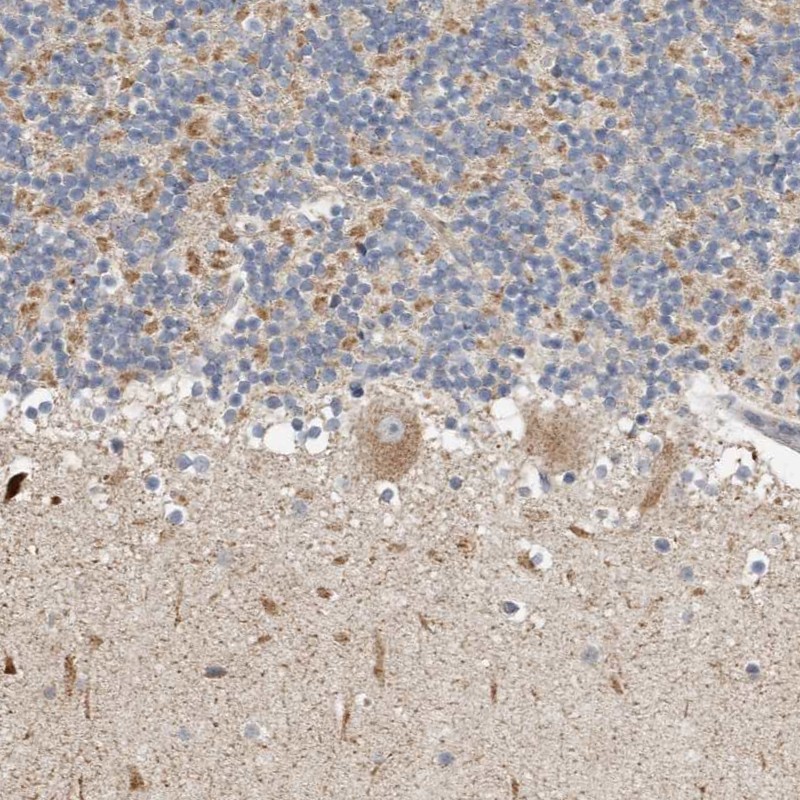

Immunohistochemical staining of human cerebellum shows moderate cytoplasmic positivity in Purkinje cells and cells in granular layer.